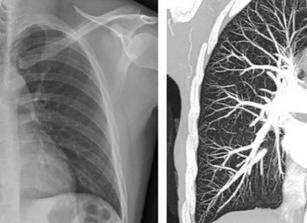

Как выглядят лёгкие без патологий?

На снимке здоровые лёгкие отличаются мешковидной формой и имеют симметричные поля. Отсутствуют очаговые либо инфильтративные тени. Корни стандартных размеров, отличаются чёткой структурой и отсутствием расширений.

В здоровом органе не задерживаются лучи. Поэтому на рентгеновском снимке лёгкие однородные и без пятен. Возле корней в центре заметна кровеносная сетка.

Для уточнения диагноза врач назначает компьютерную томографию или рентген лёгких. В отличие от томографии, рентгенография позволяет получить изображение в одной плоскости. На снимке не всегда видны новообразования на ранних стадиях.

Преимущества КТ лёгких:

1. Высокая разрешающая способность.

2. Отсутствие закрытых зон.

3. Метод позволяет оценить размеры исследуемого органа.

4. За счет применения прикладных программ, КТ позволяет получить дополнительную информацию.

Преимущества рентгенографии:

• низкая доза облучения, в сравнении с КТ;

• низкая стоимость;

• доступность, поскольку рентгенологическое оборудование присутствует практически во всех лечебных учреждениях.